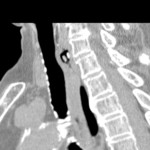

[画像診断]脊柱管内嚢胞の鑑別診断について 2010-06-29